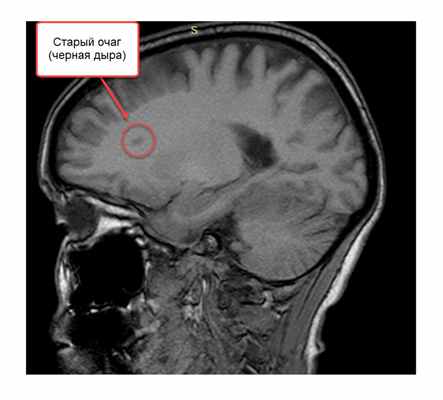

Кроме активных, копящих контраст очагов на T1-взвешенном изображении видны старые многолетние очаги, внутри которых идет или произошел процесс разрушения аксонов (отростков нейронов). Их обозначают термином «черная дыра» (black holes). При нахождении таких очагов мы говорим, что рассеянному склерозу уже несколько лет.